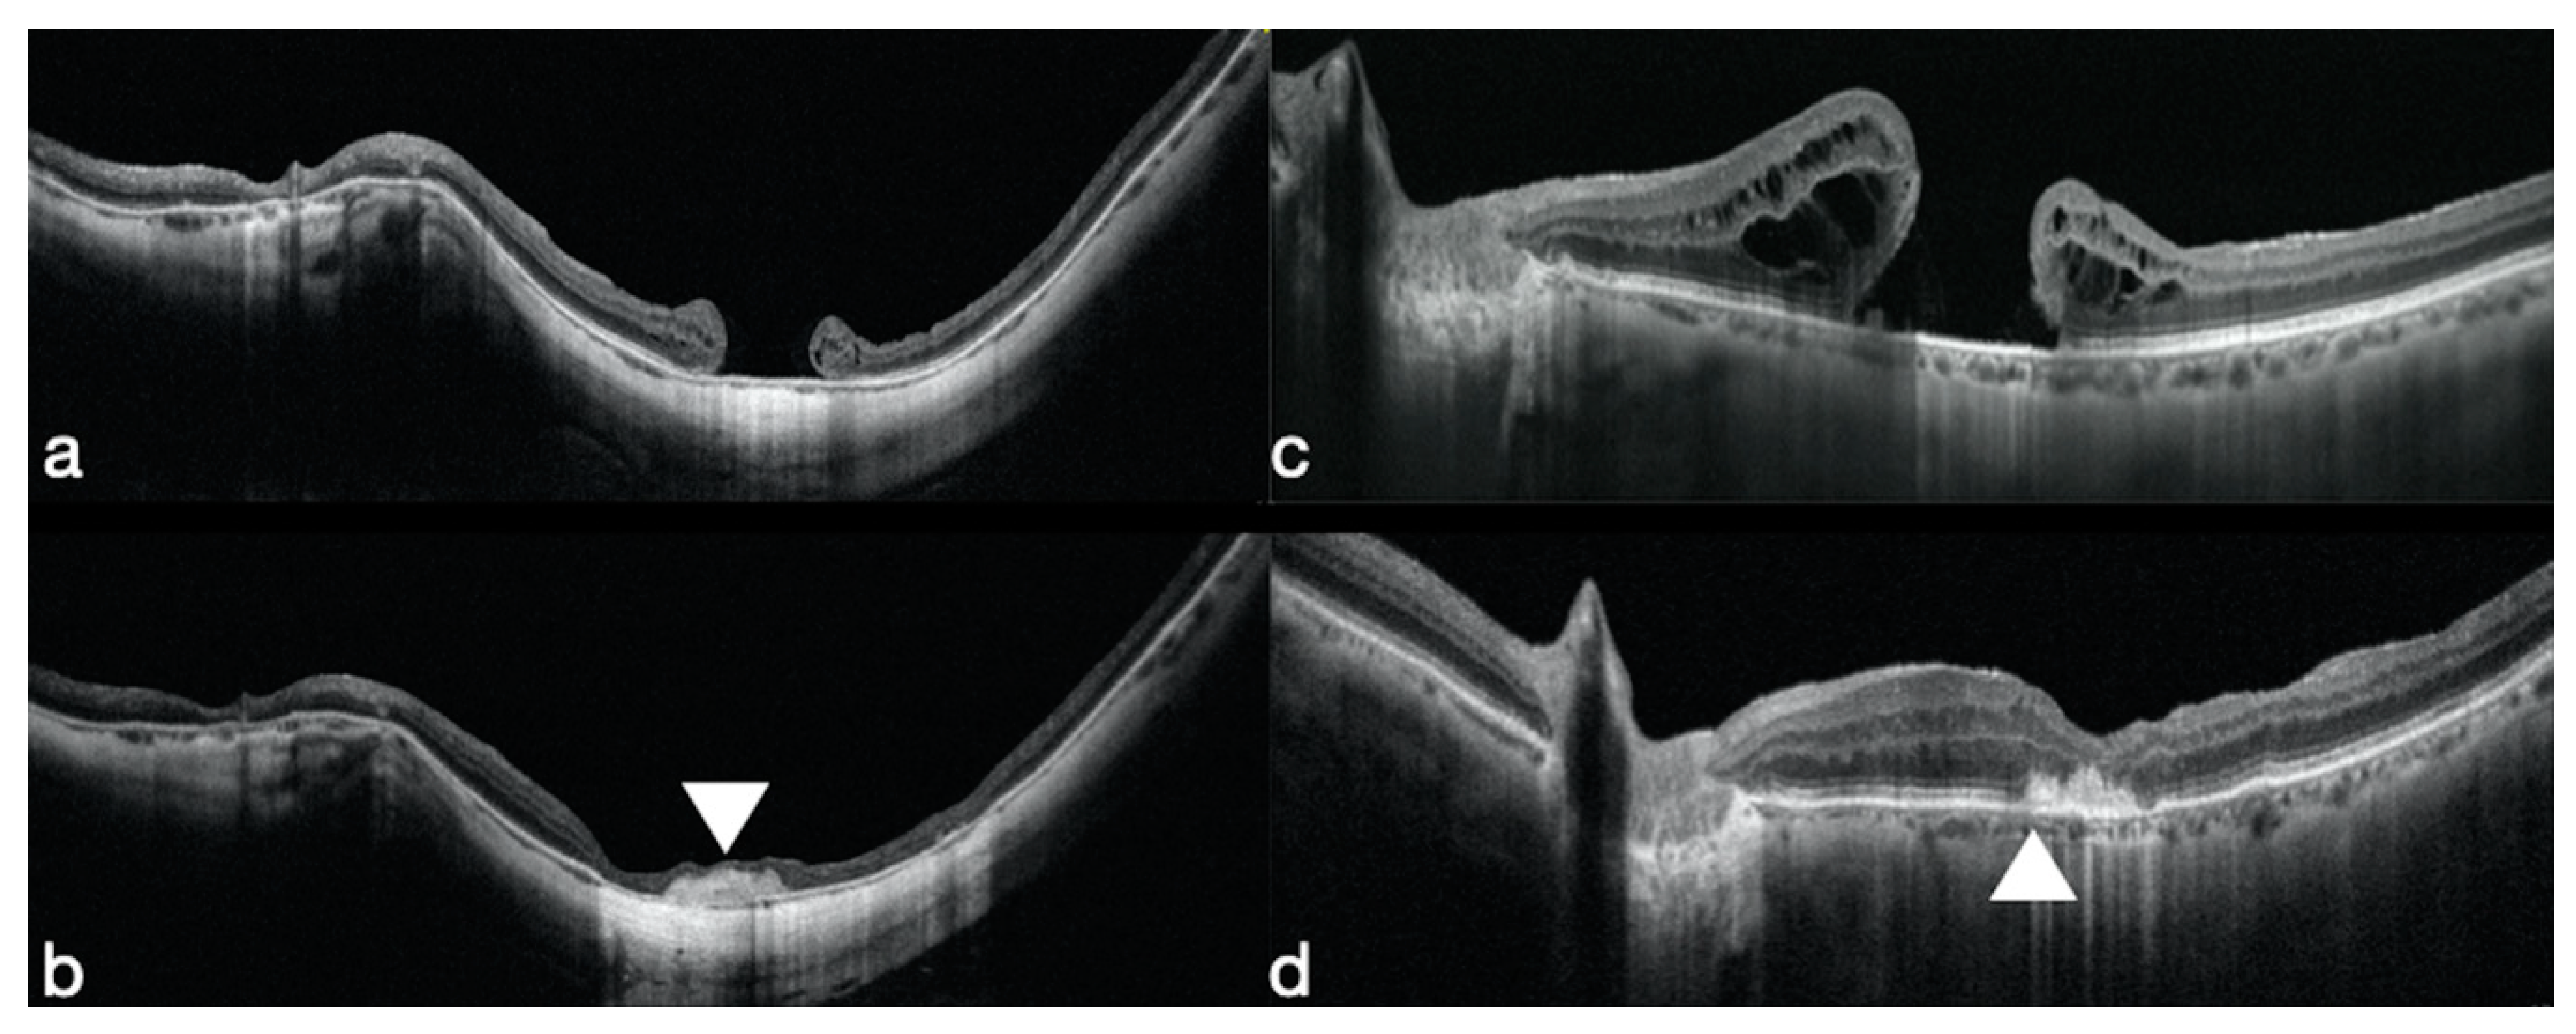

3.1. Macular Holes that Failed to Close

- Rizzo, S.; Caporossi, T.; Tartaro, R.; Finocchio, L.; Franco, F.; Barca, F.; Giansanti, F. A Human Amniotic Membrane Plug to Promote Retinal Breaks Repair and Recurrent Macular Hole Closure. Retina 2019, 39 (Suppl. 1), S95–S103. [Google Scholar] [CrossRef]

- Kang, S.W.; Ahn, K.; Ham, D.I. Types of macular hole closure and their clinical implications. Br. J. Ophthalmol. 2003, 87, 1015–1019. [Google Scholar] [CrossRef]